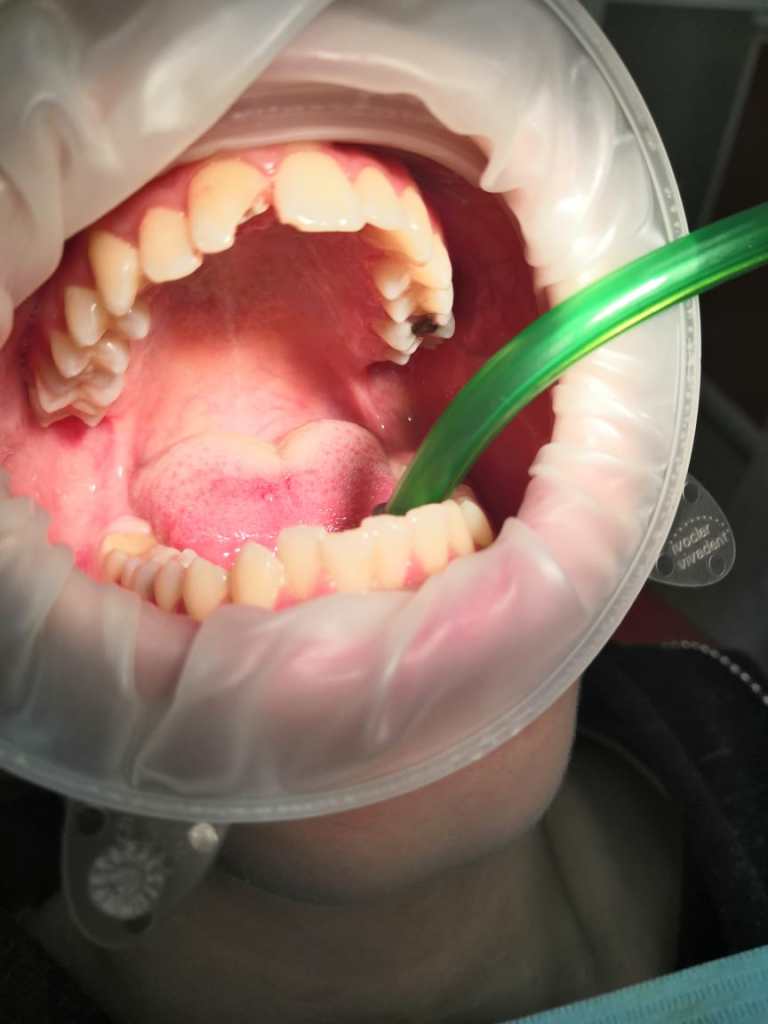

Клинический случай : скол переднего зуба 1/2, (была предложена реставрация) восстановлен стекловолоконным штифтом и сделана реставрация гелиокомпозитом